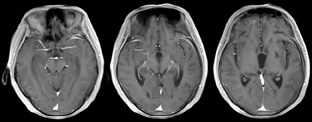

患者女性,72岁,主因渐进性右肢力弱9个月、记忆力减退3个月、错认1周于2015年6月17日入天津市环湖医院。患者于入院前9个月渐感做家务时右手无名指、小指力弱,遂就诊于天津市某综合医院,行头颅CT检查(图1),考虑脑梗死,给予输液治疗2周,此症状渐进性加重,累及中指及右手。于入院前3个月,患者因右手持物力弱、右下肢行走无力、记忆力减退、近期发生过的事情记不起来,再次就诊于天津市某中医医院,行头部MRI检查(图2),FLAIR序列可见双侧颞叶内侧面、海马区高信号影。按照脑梗死给予输液治疗,并口服阿司匹林、阿托伐他汀治疗。于入院前1周,患者右肢无力较前加重,右手持物不稳,右下肢站立及行走需搀扶,并数次跌倒。家属发现其偶有面孔错认,把自己的亲人认错。为进一步诊治收入院。自发病以来,患者无明显头痛及头晕,无视物旋转及视物成双,无恶心呕吐,无耳聋耳鸣,无肢体麻木及抽搐,无意识障碍,存在情绪低落、兴趣减少、食欲下降,体重3个月内减轻5 kg。既往史:有高血压病史20余年,血压最高达160/100 mmHg (1 mmHg=0.133 kPa),平时口服缬沙坦80 mg (1次/d)降压治疗,血压维持在120~130/90 mmHg。入院后神经科体检:意识清楚、构音障碍,双瞳孔等大等圆,光反射(+),眼动可,眼位居中,无眼震及复视,右侧鼻唇沟稍浅,伸舌尚居中,颈软,右肢肌力Ⅳ级,左肢肌力Ⅴ级,肌张力可,腱反射(++),双侧巴宾斯基征(-),右面部及右侧肢体浅感觉异常,双侧共济检查稳准。高级神经活动认知功能检查:简易精神状态检查评分12分,蒙特利尔认知评估量表评分7分,定向力、回忆能力、计算力、语言重复流畅性、执行功能、视空间结构等领域均受累。实验室检查阳性结果:血常规示中性粒细胞百分比83.0%(正常值40%~75%),血小板计数68×109/L[正常值(125~350)×109/L];红细胞沉降率37.00 mm/h(正常值0~15 mm/h),乳酸脱氢酶265 U/L(正常值135~225 U/L];甲状腺功能全项:三碘甲状腺原氨酸1.00 nmol/L(正常值1.3~3.1 nmol/L);血液三项:叶酸4.08 ng/ml(正常值4.6~34.8 ng/ml)。超敏C反应蛋白、乙型肝炎、梅毒血清学检查结果正常。肺癌和肝脏、胃肠、盆腔肿瘤标志物检查结果正常。入院后行腰椎穿刺检查,压力200 mmH2O(1 mmH2O=0.009 8 kPa);脑脊液常规:总细胞数382×106/L,白细胞数2×106/L[正常成人(0~8)×106/L] ;脑脊液生化:氯化物117 mmol/L(正常值120~132 mmol/L],蛋白1.18 g/L(正常值0.15~0.45 g/L),乳酸5.4 mmol/L(正常值0.6~2.2 mmol/L)。脑脊液免疫功能:白蛋白714.00 mg/L(正常值0~350 mg/L),免疫球蛋白A 6.89 mg/L(正常值0.1~5 mg/L),免疫球蛋白G 56.30 mg/L(正常值0.1~34 mg/L),免疫球蛋白M 2.68 mg/L(正常值0~1.3 mg/L)。脑脊液病理检查可见大量红细胞及少量单核细胞、淋巴细胞。入院后查头颅MRI(2015年6月18日;图3)示双侧岛叶、双侧海马FLAIR高信号(较3月前增大)。增强头颅MRI(2015年6月19日;图4)示双侧颞极、双侧海马、双侧岛叶轻度肿胀,伴异常信号,增强后未见明显异常强化。胸片示主动脉硬化,腹部超声示肝胆胰脾未见明显异常。胸部CT、肝胆胰CT未见异常。盆腔CT示双侧附件区点状钙化影,考虑输卵管钙化。泌尿系超声未见明显异常。肌电图提示:右上肢(颈6~8)神经源性损害,重频电刺激未见明显异常。脑电图提示:清醒及睡眠脑电图各导联可见较多散在低中幅不规则慢波,以前头部为著,未见痫样波发放。副肿瘤相关抗体检查:血及脑脊液双份抗Ma2抗体检测,血为阳性(++),脑脊液阴性;抗神经元胞核抗体(Hu-Ri-Yo)、抗塌陷反应调节蛋白5(cV2)抗体、抗双载蛋白(amphiphysin)抗体阴性;N-甲基-D-天冬氨酸(NMDA)受体抗体、谷氨酸α-氨基-3-羟基-5-甲基-4-异